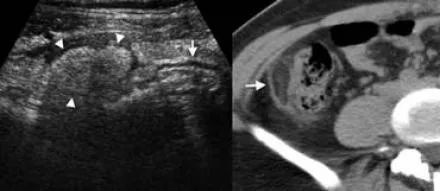

超声和CT表现包括结肠周围脂肪的炎性改变和憩室炎水平周围结肠壁节段性增厚。

下图 51岁男性右半结肠憩室炎。无增强CT显示沿盲肠壁(箭头)和正常阑尾(箭头)脂肪缠绕。超声显示炎症的原因,一个发炎的盲肠憩室(箭头)。